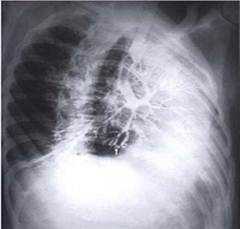

Бронхография у детей имеет особенно важное значение в связи с возможностью раннего выявления пороков развития и приобретенных заболеваний легких и своевременного их хирургического лечения. У детей Б. впервые применили Арман-Делилль и Дарбуа (P. Armand-Delille, J. Darbois, 1924). Контрастное вещество они вводили в трахею путем ее прокола в подгортанной области, исследование выполнялось под местной анестезией. Эта методика не получила широкого распространения. Широкое внедрение Б. в педиатрическую практику стало возможным только с развитием методов общего обезболивания. Выполнение поднаркозной Б. у детей наиболее оптимально.

Существуют методики, предусматривающие введение контрастного вещества через катетер при бронхоскопии. Однако наиболее щадящей является методика Б. под интратрахеальным наркозом без рентгеноскопического контроля. Исследование проводят натощак, за 30— 40 мин. до начала Б. вводят атропин в возрастной дозировке. Обезболивание — интубационный наркоз с миорелаксантами. После гипервентиляции в течение 1—1,5 мин. через интубационную трубку в трахею вводят во время апноэ катетер. Трахею с интубационной трубкой в области шеи смещают в сторону, противоположную тому легкому, в бронх к-рого хотят ввести катетер (рис. 5, 1 и 2), и затем катетер продвигают в соответствующий бронх до упора, ориентируясь на длину трахеи и бронхов у детей различного возраста. Нахождение катетера в правом или левом главном бронхе определяют, присоединяя к катетеру баллон Ричардсона и нагнетая воздух; при выслушивании фонендоскопом шум вводимого воздуха определяется над правой или левой половиной грудной клетки (рис. 5, 3).

Заполнение контрастным веществом начинают с бронха нижней доли, затем катетер подтягивают, продолжая вводить контрастное вещество. Больной лежит на боку, на исследуемой стороне — в этом положении делают первую рентгенограмму; вторую рентгенограмму производят в положении ребенка на спине. При известном навыке исследование одного легкого занимает не более 2—3 мин. Контрастное вещество из бронхов удаляют электроотсосом. Проводят вентиляцию, затем приступают к исследованию другого легкого.

Предпочтительнее пользоваться водорастворимыми контрастными веществами. Количество контрастного вещества, необходимое для контрастирования бронхов одного легкого, можно определять по следующей схеме: 4 мл + возраст больного в годах. В бронх нижней доли вводят половину этого количества, вторую половину — постепенно по мере подтягивания катетера. Расстояние, на к-рое следует подтягивать катетер, у детей до 1 года — 1,5 см; 2—3 лет — 2 см; 4—7 лет — 3—4 см; 8—12 лет — 5—7 см; 13—15 лет — 10—12 см.